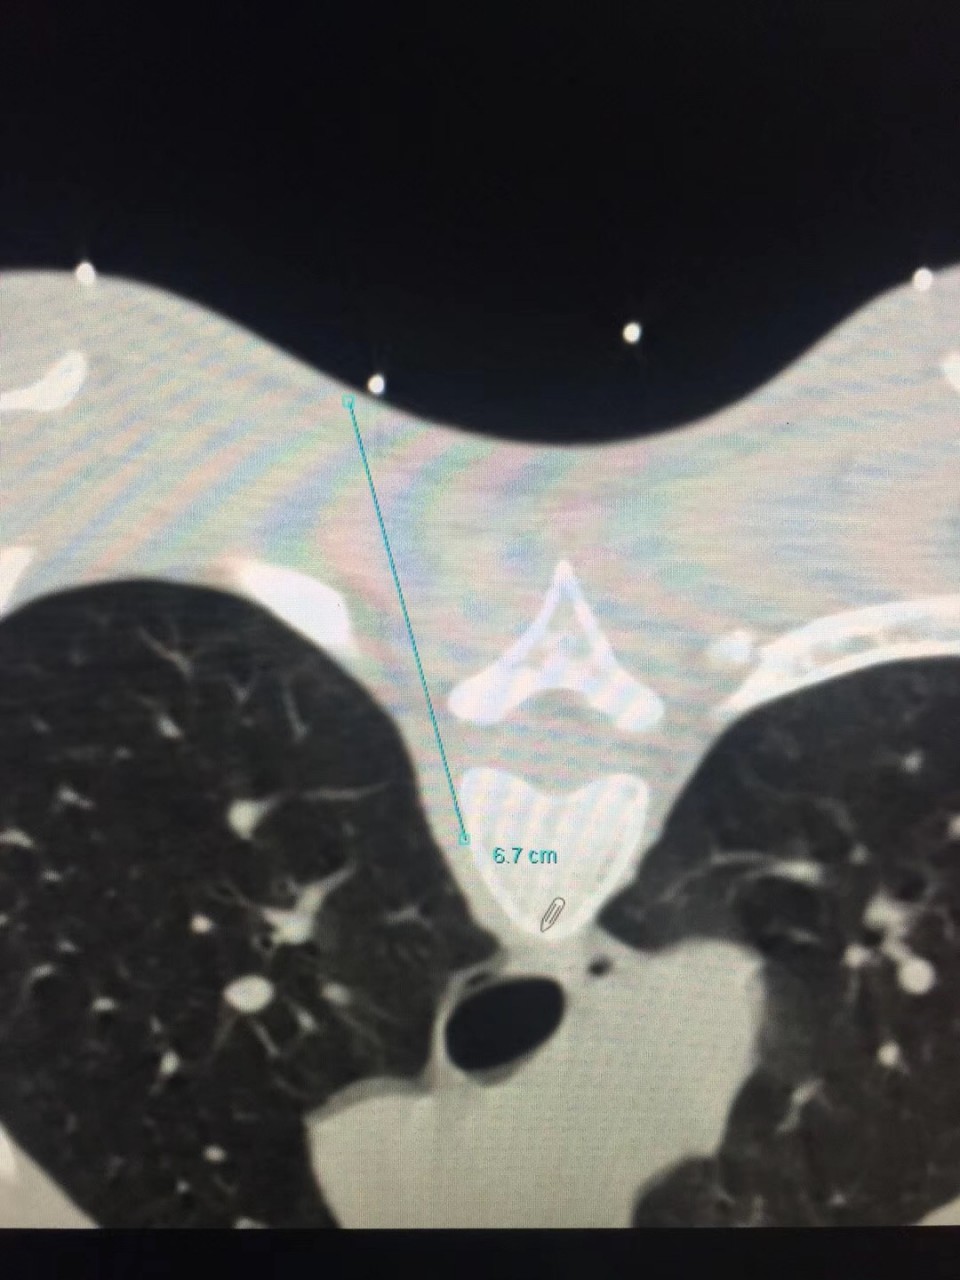

近日,疼痛科接诊了一位18岁的多汗症患者,该患者反复双足发汗多年,伴手上皮肤脱落。曾就诊于省内外多家医院,但均未获得满意的疗效。听闻安徽医科大学第一附属医院疼痛科是一种以微创介入方法治疗各种疑难病痛的科室,遂前往就诊。疼痛科副主任医师宋阳在对该患者病情特点进行综合的分析后决定对其进行CT引导下胸交感神经链无水酒精化学毁损术。当日手术结束后该患者立马感觉到双手不再是以前那样冰冷,逐渐回复了正常的温度,且发汗症状完全消失。在观察了数日之后无任何的复发症状,负责该患者的副主任医师宋阳称,通过无水酒精的化学毁损作用中断汗腺神经分泌的神经传递过程,可永久的减少出汗,达到临床治愈水平。

对于诊断明确的原发局部性多汗症患者,传统的治疗手段有局部及全身药物治疗以及激光、微波等物理疗法。目前比较主流的有CT引导下经皮穿刺胸交感神经化学阻滞及外科手术治疗。其中CT引导下交感神经链阻滞技术成功率甚至可达100%,治疗效果与胸腔镜下交感神经链切断术效果相当,应用无水酒精能达到对交感神经链的功能有效长久的阻滞,达到良好的治疗效果,且创伤更小、并发症更少。胸腔镜下交感神经切断术是治疗手、头面部及腋窝多汗症的一种二线治疗方案。但其术后疼痛、气胸、神经病变累及上肢、霍纳综合症以及代偿性多汗症发生率较高。